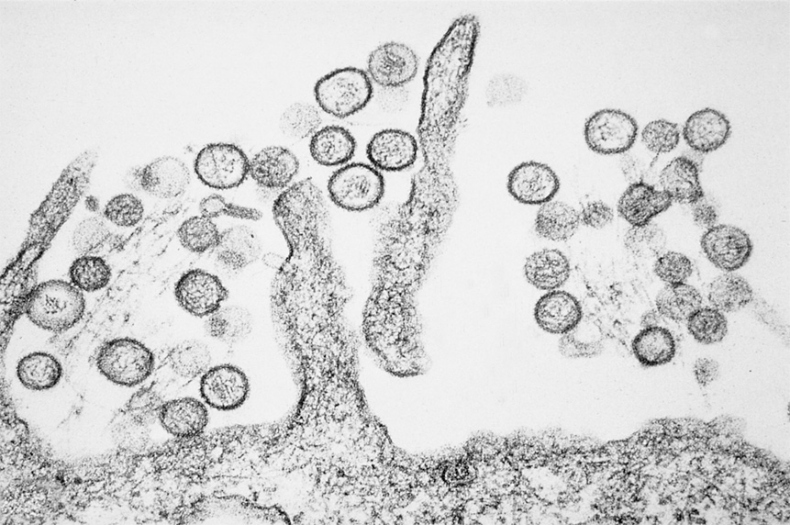

Рассмотрение историй болезни этих пациентов и анализ образцов крови и тканей при вскрытии вирусологами CDC показали, что причиной был один инфекционный агент. (Рисунок 12.1 на вклейке.) Этот агент был идентифицирован как хантавирус3, член семейства трансмиссивных вирусов Bunyaviridae4. Затем ученые, специалисты по молекулярным методам изучения генома вируса, сообщили, что выделенный хантавирус сильно отличается от известных штаммов, которые обычно вызывают геморрагические лихорадки и заболевания почек, но не острое повреждение легких. Обнаруженное заболевание было названо хантавирусным пульмональным синдромом1-3. Государственное наблюдение за хантавирусными инфекциями в Соединенных Штатах было тогда инициировано Центром инфекционных заболеваний. В 1995 году болезнь стали отслеживать и регистрировать на национальном уровне. К марту 1995 года в 20 штатах было выявлено около 106 пациентов с хантавирусным пульмональным синдромом, более половины из них погибли. Обычно симптомы включали лихорадку, мышечную боль, кашель, тошноту, рвоту и головную боль, которые продолжались от 4 до 15 дней и в итоге приводили к госпитализации пациентов. При поступлении в больницу у большинства пациентов отмечались лихорадка, низкое кровяное давление, малое количество тромбоцитов (клеток, необходимых для свертывания крови) и аномалии (если говорить точнее, инфильтраты) в легких, заметные на рентгеновских снимках. Какое-то время спустя у пациентов развивался отек легких: состояние, при котором легкие постепенно наполняются внесосудистой жидкостью. По сей день никто точно не знает, каким образом хантавирус провоцирует такие симптомы, хотя недавно обнаруженные свидетельства предполагают высвобождение определенных белков: возможно, цитокинов и хемокинов, которые во многом регулируют иммунный ответ организма. Во время воспаления, вызванного инфекцией, важную роль в патогенезе заболевания играет так называемый цитокиновый шторм. Никаких других методов лечения, кроме поддерживающей терапии и профилактики, для облегчения симптомов хантавирусной инфекции не существует. После того как информация о вирусе стала достоянием общественности, на юго-западе США сократился поток туристов, пришли в упадок соответствующие отрасли бизнеса. Поэтому первоначальное название вируса, «вирус четырех углов», отсылающее к региону, где болезнь возникла, было изменено. Вследствие политической и экономической необходимости сейчас вирус зовется Sin Nombre virus – «вирус без названия»1,5. Так «вирус четырех углов» обрел новую политическую корректность.

РИСУНОК 12.1. Электронная микрофотография хантавируса